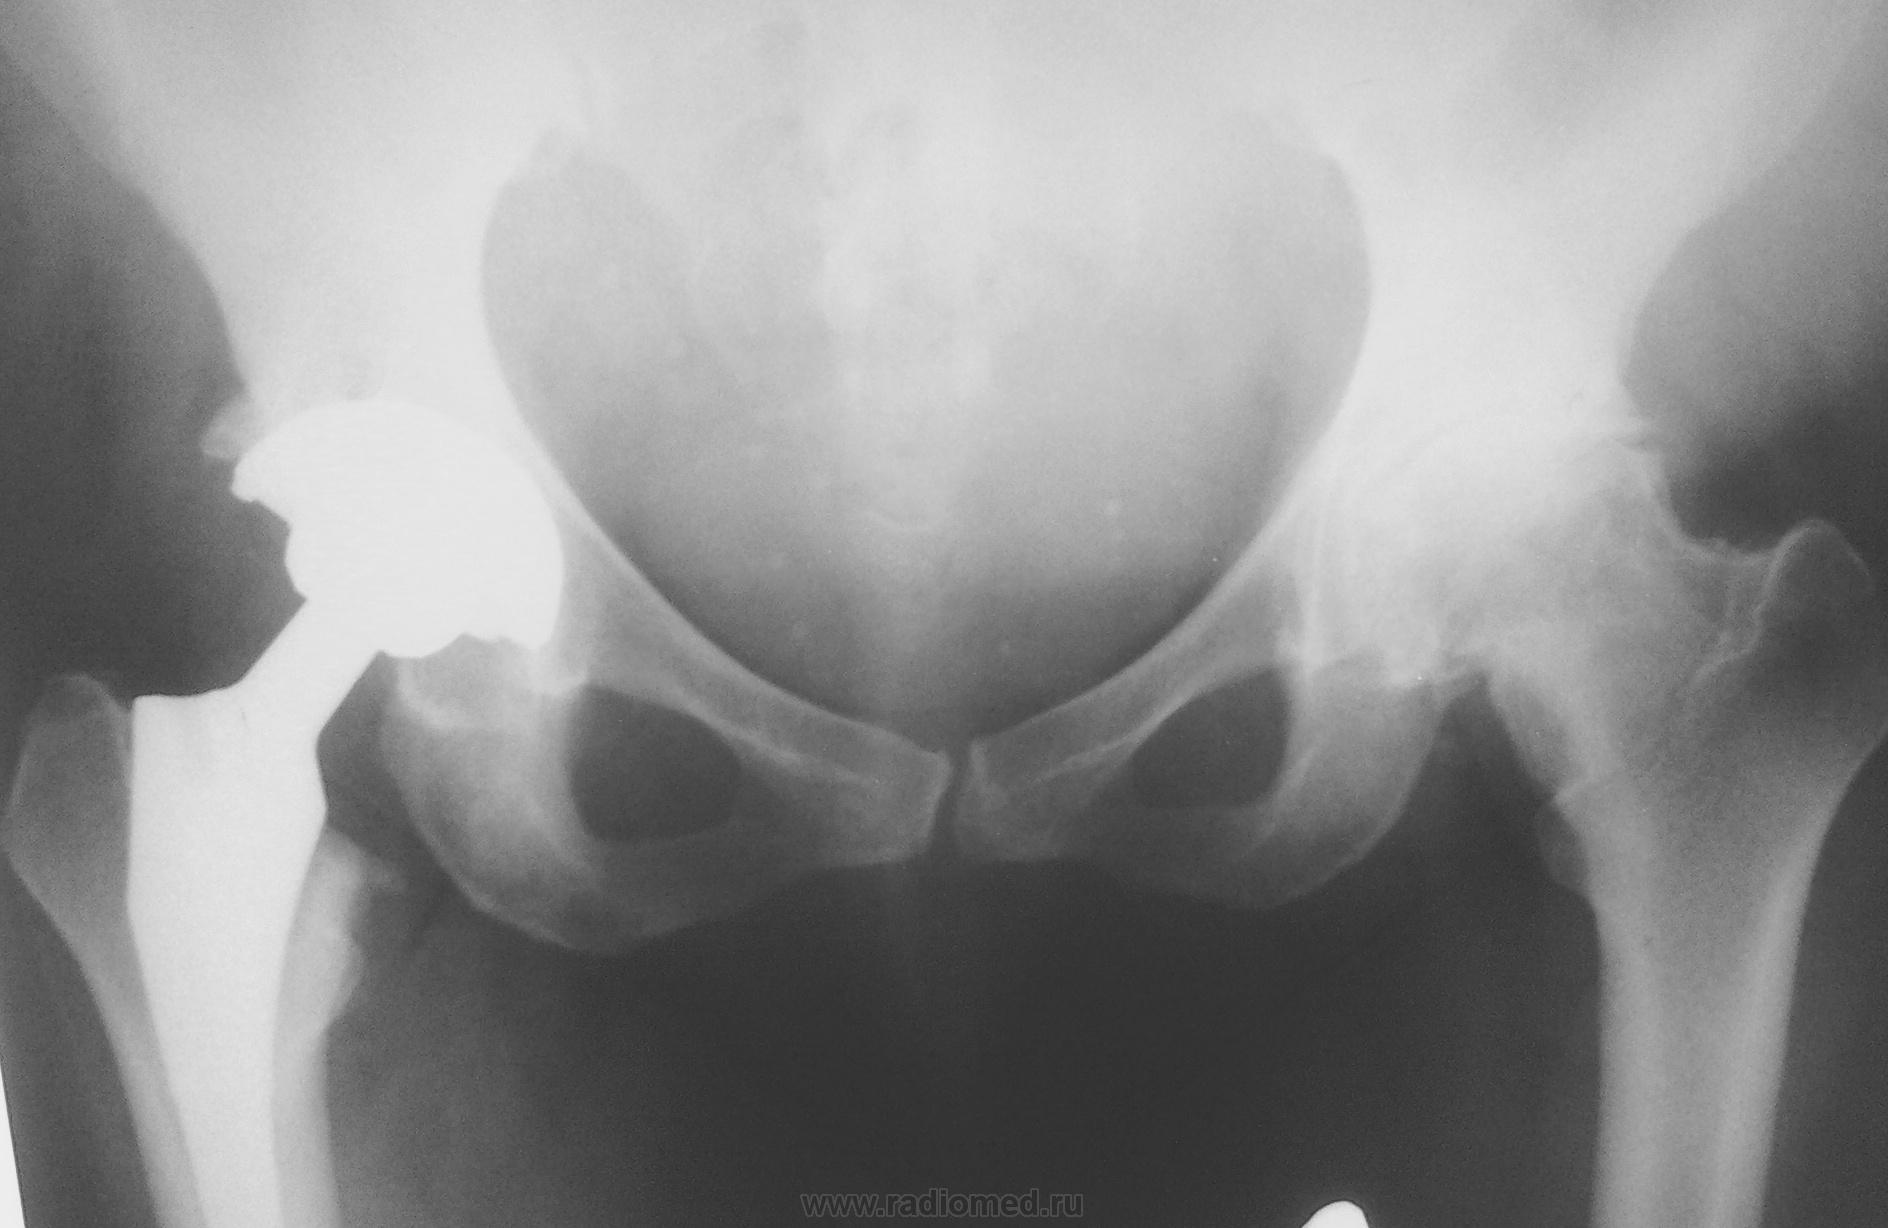

Пол пациента: Женский пол Тип патологии: Другое Область исследования: Скелетно-мышечная система Методы исследования: Rg Попросили описать представленный снимок,справа понятно -эндопротез,слева артроз,вопрос в том чем объяснить дополнительную тень по медиальному контуру шейки бедренной кости слева?или не заострять вообще на этом внимание? ID:35610 Ср, 19/02/2014 - 21:28 #1 NIL Не на сайте Был на сайте: 2 дня 14 часов назад Зарегистрирован: 25.11.2013 - 20:50 Публикации: 18207 Тень костной плотности. Контуры чёткие. Я бы назвала это явление периостоз шейки левого бедра.(м.б. перелом в анамнезе?) "Слушай всех, прислушивайся к немногим, решай сам".© Ср, 19/02/2014 - 22:14 #2 nelly Не на сайте Был на сайте: 11 лет 1 месяц назад Зарегистрирован: 11.07.2011 - 19:19 Публикации: 328 про перелом спрашивала-сказала,что не было травмы этого сустава Ср, 19/02/2014 - 22:48 #3 NIL Не на сайте Был на сайте: 2 дня 14 часов назад Зарегистрирован: 25.11.2013 - 20:50 Публикации: 18207 А вторую проекцию сделать не получится? "Слушай всех, прислушивайся к немногим, решай сам".© Чт, 20/02/2014 - 00:04 #4 Андрей Юрьевич Не на сайте Был на сайте: 2 недели 1 день назад Зарегистрирован: 16.11.2008 - 22:16 Публикации: 18098 Если вопрос возник, его надо разрешать: снять с внутренней ротацией бедра. Андрей Юрьевич

Тень костной плотности. Контуры чёткие. Я бы назвала это явление периостоз шейки левого бедра.(м.б. перелом в анамнезе?)

про перелом спрашивала-сказала,что не было травмы этого сустава

Если вопрос возник, его надо разрешать: снять с внутренней ротацией бедра.